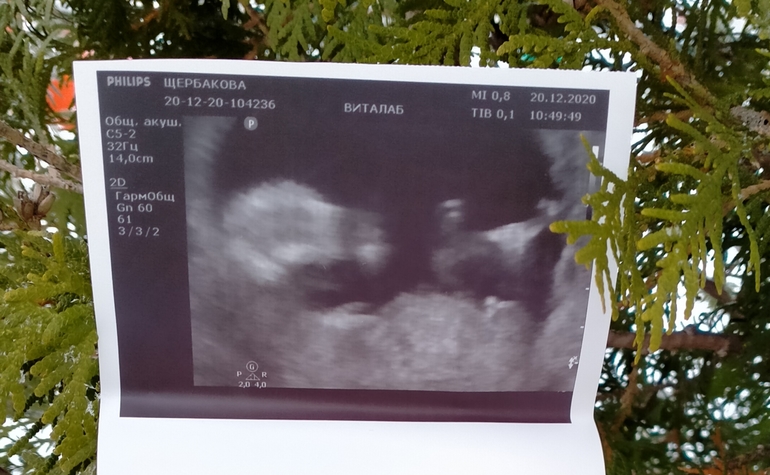

Узи в 16недель 💙счастливая))

Самое дорогое услышала 🤍моего крохи.Весим+-(132гр) забавнный такой,места у него так ещё полно, активный руки/ ноги упирает в стенки..Но я пока не чувствую шевелений,хоть я и "прозрачная",как ск врач , даже шейку смогли поменять через живот 🤭

Два разных врача определили один и тот же пол,думаю совмений не останется.Кружочек окрасила🤪 Мой в врач в центре, вообще долго смеялась когда увидела"ЭТО"😅🤣😅такой явный как в книге.Фото сделала от души 🤣🤣🤣

Вам видно??!!Решил так,чтоб без притензий🤭😅